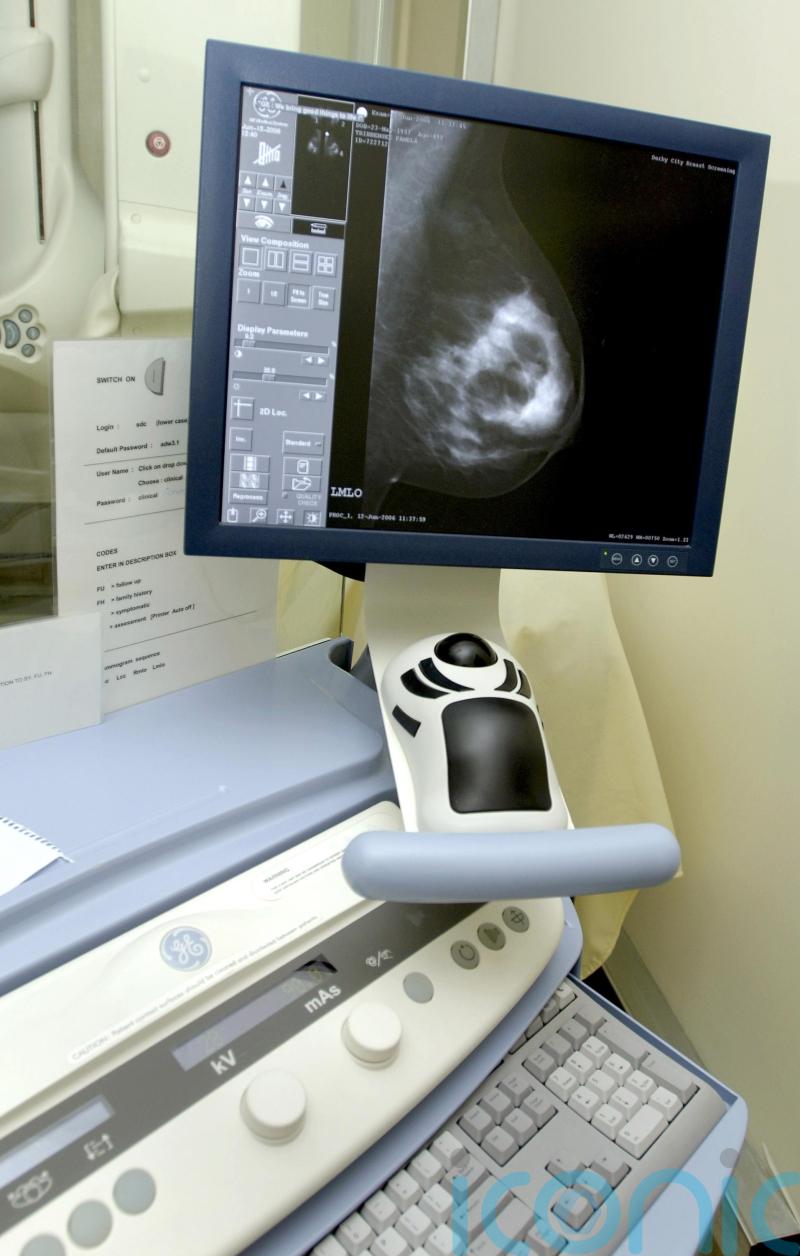

Breast cancer spreads at night, new research suggests

Breast cancer spreads most while patients are sleeping, new research suggests.

According to the World Health Organisation (WHO), breast cancer is one of the most common forms of cancer, and each year around 2.3 million people worldwide contract the disease.